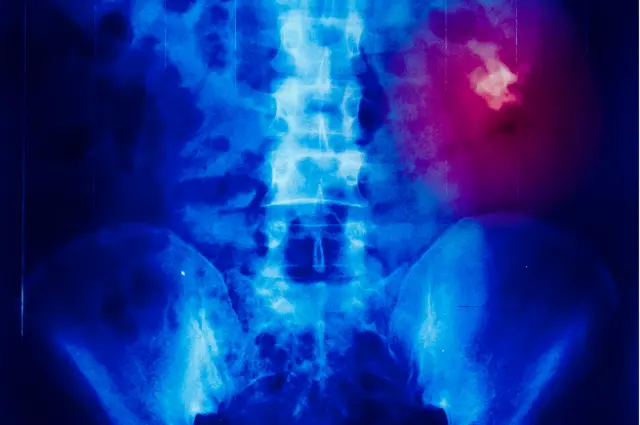

En enero, terminé en emergencias con un dolor en el abdomen que ya no me dejaba estar de pie derecho.

Después de un escáner, y de retorcerme de la manera más indigna, el médico me dijo que tenía cálculos renales, probablemente causados por una ingesta desproporcionadamente alta de proteínas, que mi cuerpo simplemente no pudo procesar y convirtió en depósitos calcificados en los riñones.

Cuando estas pequeñas "piedras" se atascan... duele.